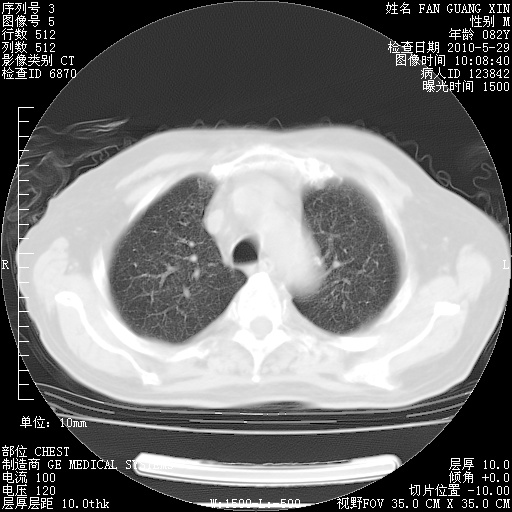

再治疗10天后的肺部CT